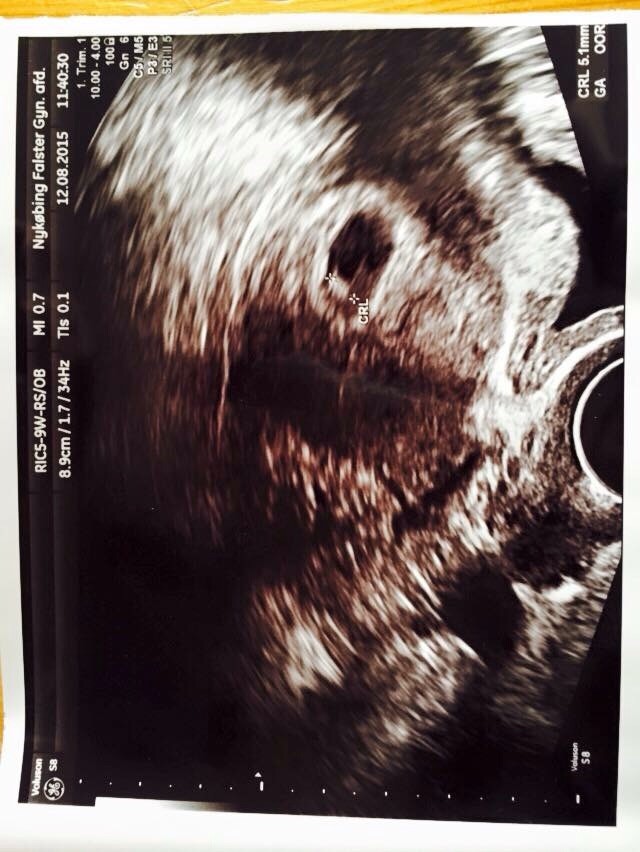

Skanningen gik godt idag der var hjerteblink og et lille foster på 5 mm

Vedhæftede fotos (klik for at se i fuld størrelse)